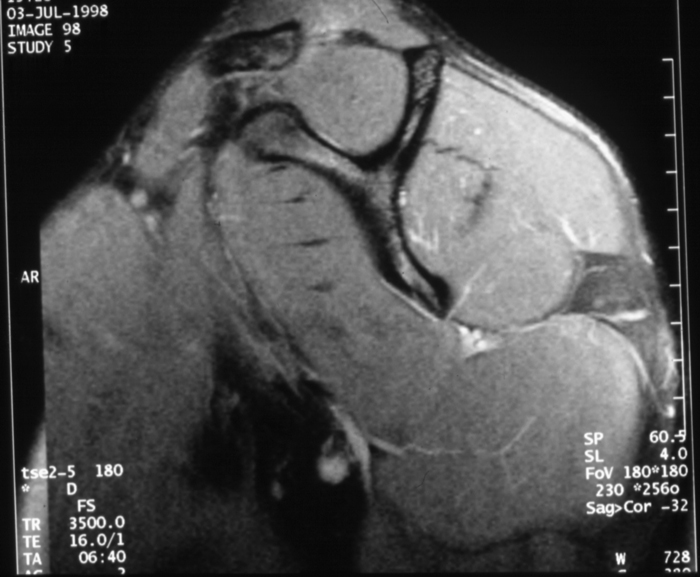

Radiology MS 196 - Normal MR of the Left Shoulder

Identify: Medial Sagittal - coracoid process, spine of scapula, clavicle, supraspinatus muscle, infraspinatus muscle, subscapularis muscle